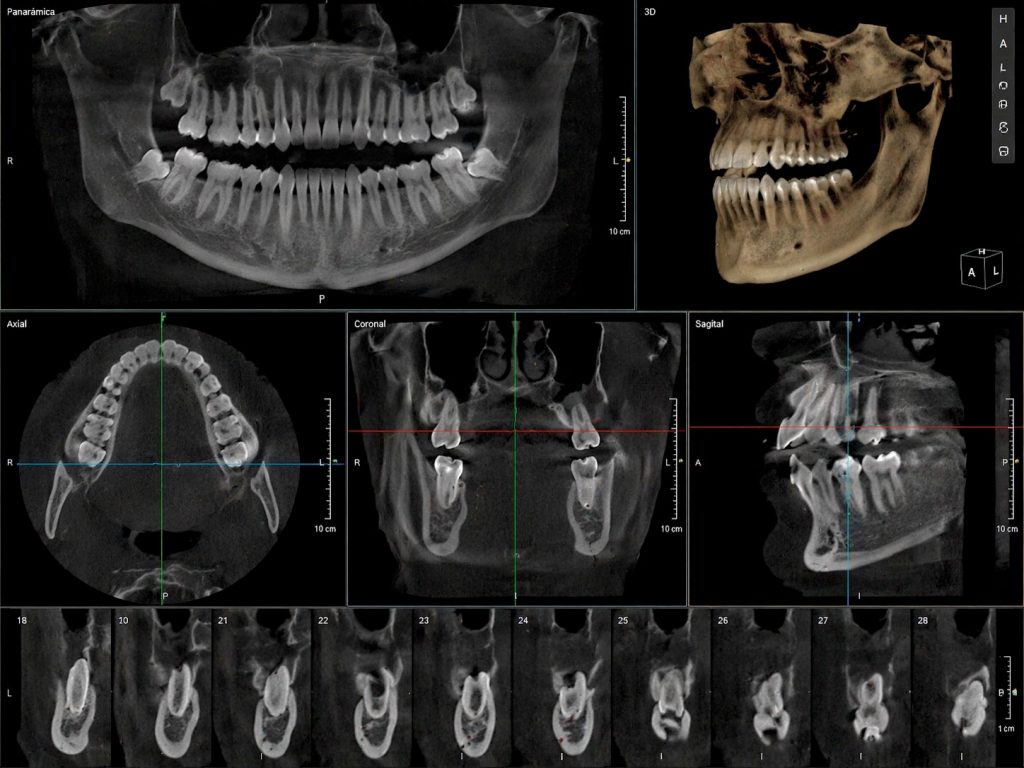

La radiografía 3D o CBCT es una tecnología de diagnóstico por imagen que genera una reconstrucción tridimensional de las estructuras dentales, óseas y nerviosas del paciente.

A diferencia de las radiografías convencionales, el CBCT permite visualizar:

- Dientes desde todos los ángulos

- Hueso maxilar y mandibular con gran detalle

- Nervios y estructuras anatómicas sensibles

- Senos maxilares

- Posición exacta de piezas dentales incluidas